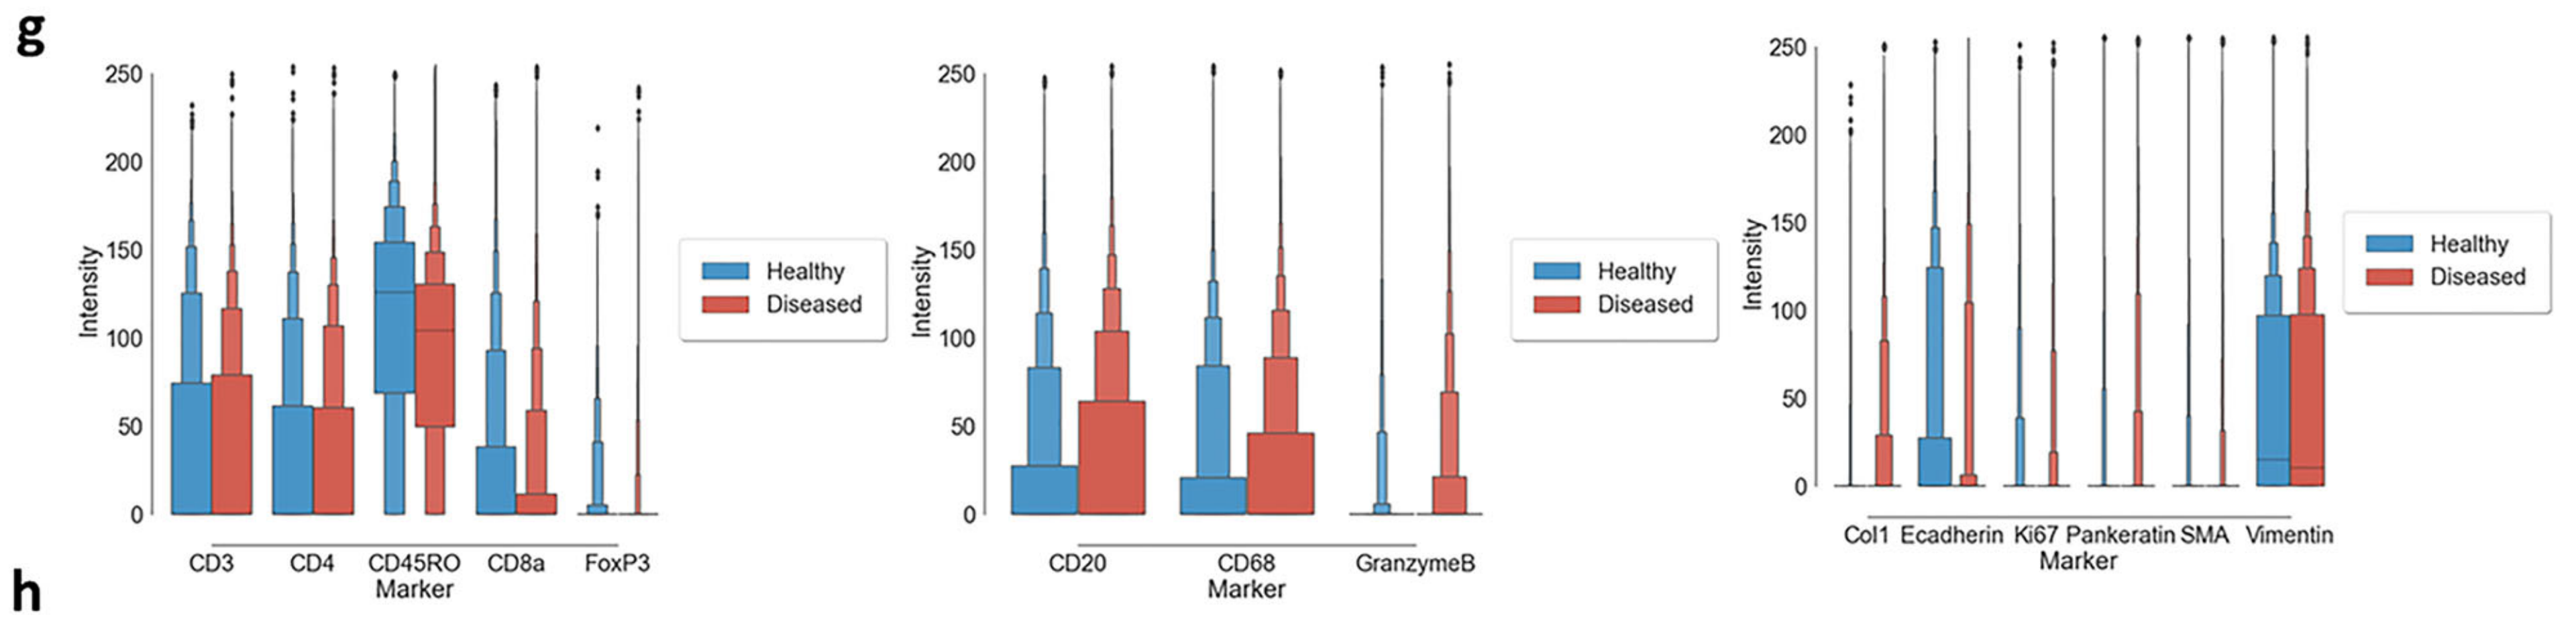

Li X. et al. - 2025

SPEX: A modular end-to-end platform for high-plex tissue spatial omics analysis

Condition Dimension

Categorical

Data Components

Biological AnnotationGene Expression Matrix

Metadata

None

Modality

Proteomics

Resolution of observation

Cellular

Visualized Elements

Statistic

How does expression of a gene differ across patient categories?

Biological

Molecular

Abstraction

Complete

Chart Type

Boxplot

Communicative/Contextualization

Annotation

Comparative Design

Juxtaposition

Layout

Linear

Scalability Strategy

Summay/Aggregate